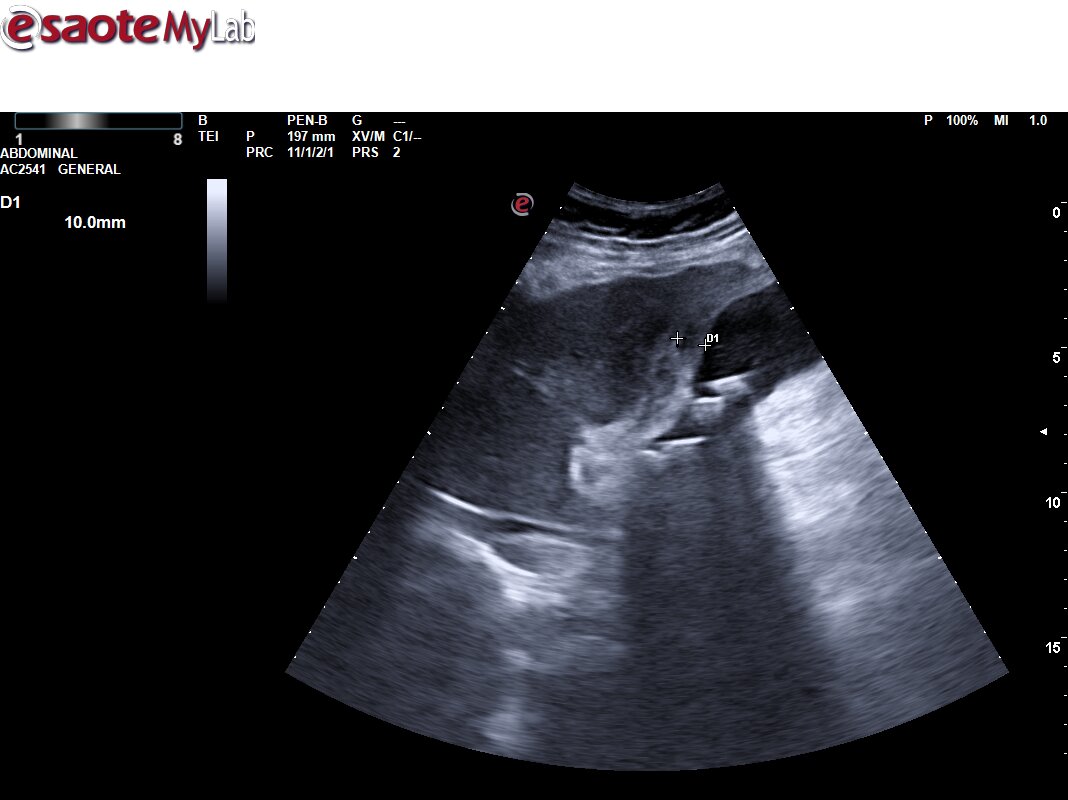

Ecografía primaria. Se aprecia vesícula con aumento de la pared de la vesícula biliar de unos 10 mm, con signos flogóticos (aumento de captación Doppler y líquido libre perivesicular), con contenido hiperecogénico en su interior con sombra posterior, y dilatación de vía intrahepática. Vía extrahepática no valorable por interposición de gases. Colecistitis. Dilatación de vía intrahepática.